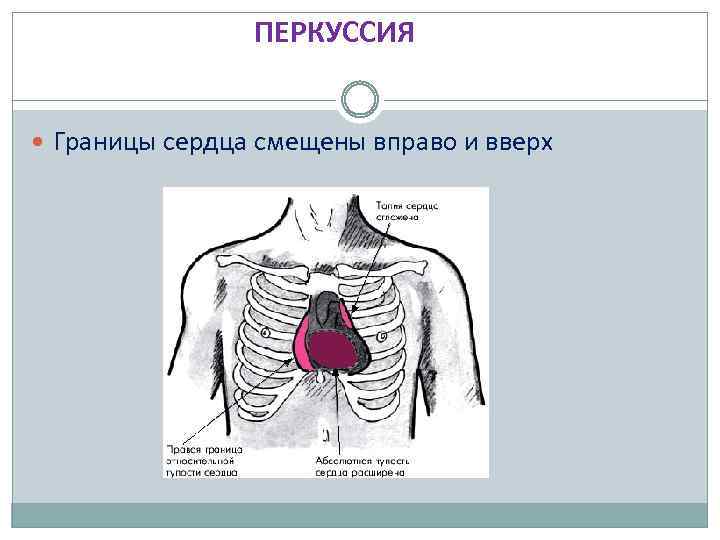

ПЕРКУССИЯ Границы сердца смещены вправо и вверх